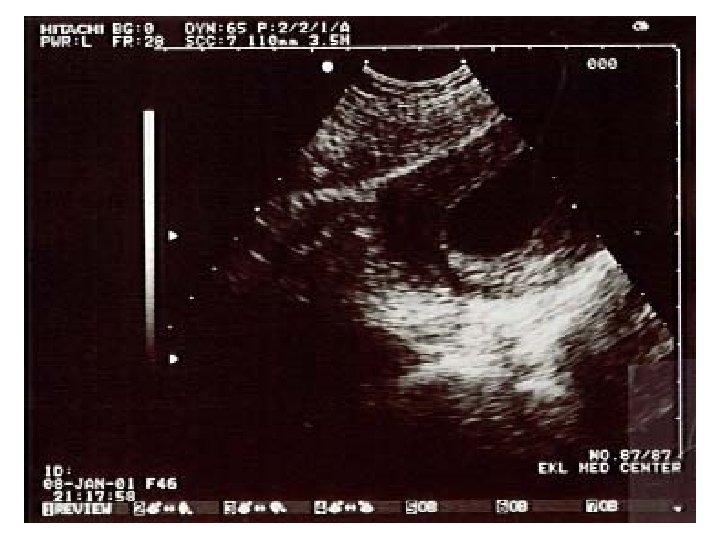

Ultrasound imaging: carotid artery • Doppler imaging looks at artery • Get image and trace of blood flow • This is a healthy artery. The flow is smooth and all in the same direction, like water in a large, slow river